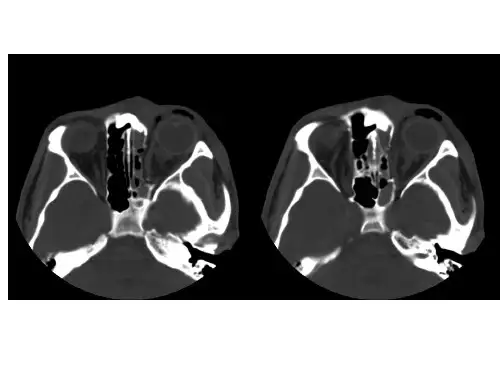

右侧颞骨岩部骨折

泪 骨 骨 折

筛骨纸板骨折

鼻骨骨折

上 颌 骨 额 突 骨

折